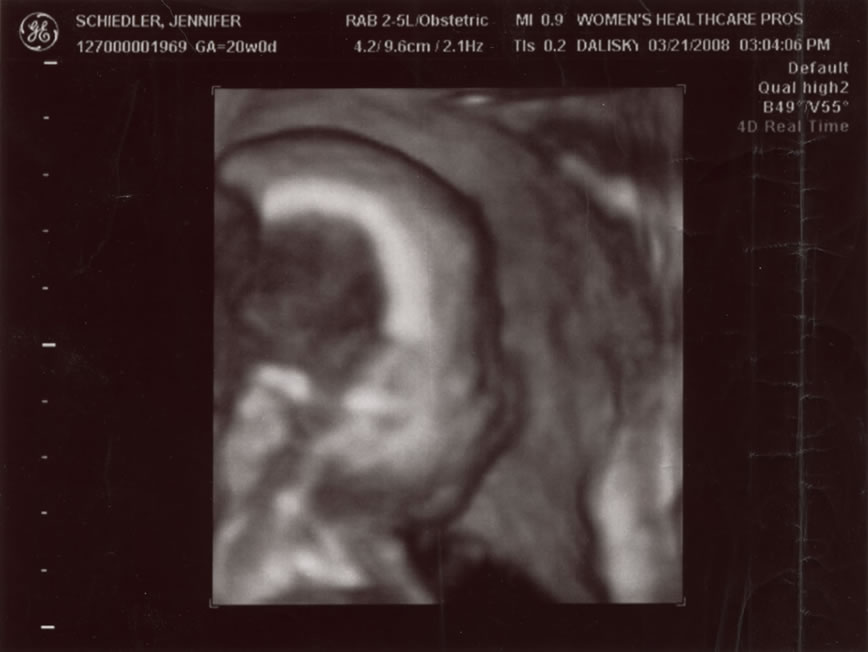

You can see fingers if you look close  5 of 5